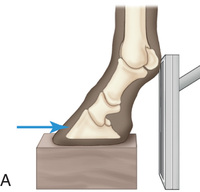

The most significant safety action is to increase one's distance from the primary beam through the use of a cassette holder (Fig. 24.3) and the use of a tripod to hold the x-ray unit if space and circumstances allow. Because the construction of x-ray machines does not allow the primary beam to be centered less than about 10 cm (4 inches) from the ground, a positioning block is needed to raise the affected foot (Fig. 24.4) for most views of the foot and pastern.

If using a foot block, have it high enough so that the beam can be directed in a horizontal plane on the area of interest. Ideally, the block should have a slot to support the cassette close to the limb to minimize distortion (Fig. 24.4D). If only the lateromedial view of the digit is needed, then shoe removal, sole cleaning, and foot trimming are not essential. For equal weight-bearing, both front feet should be on a foot block. If only the affected foot is placed on the block, improper pressure of the distal limb joints may affect the accuracy of the diagnosis.